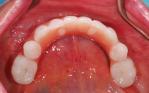

Replacement of all the teeth with an upper overdenture that clicks onto five implant fixtures and a fixed lower titanium framework acrylic bridge on four implant fixtures.

After